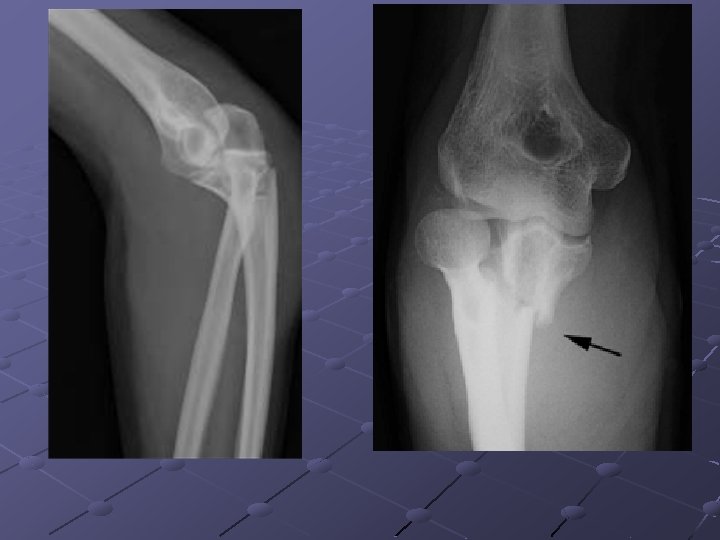

Quelle coude ? Quelle incidence ? Quelle patho ? G G Face Rupture de corticale : fracture Profil Fracture, arrachement de l’olécrane Associée à une luxation radio-humérale